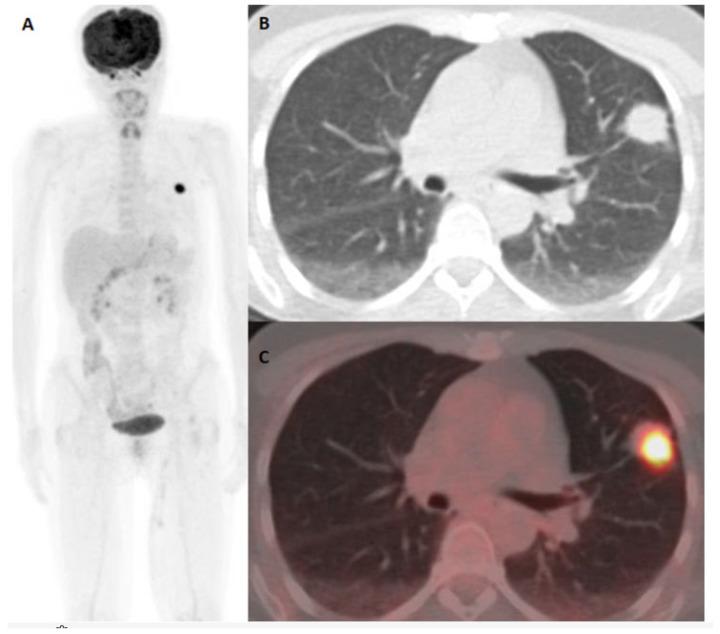

The global increase in the incidence of malignant melanoma, without significant changes in the mortality rate, may be influenced by the changes in the diagnostic approach and criteria, and the impact of innovative therapies on the survival of patients. Advances in treatment options, influencing prolonged survival, are bringing up a strong need for close surveillance of melanoma patients. In this observational, retrospective, and single-center study, we determined the impact of 18F-FDG PET/CT diagnostics on the outcomes and survival of malignant melanoma patients at different stages from an extensive and unselected group in a real-life clinical management setting. A total number of 189 malignant melanoma patients who underwent 18F-FDG PET/CT examination in the course of the treatment at one university oncology institute during the period from January 2010 to December 2024 were included in the study, and the multifactorial impact on the outcome and survival of malignant melanoma patients was observed in regard to the differences resulting from the therapeutic approaches and the introduction of new therapeutic options and drugs. Our results indicate that 18F-FDG PET/CT is a sensitive imaging tool for the detection of predominantly distant metastases in malignant melanoma patients belonging to an extensive and unselected population in a real-world clinical setting, not only at advanced melanoma stages but also at early stages of high-risk patients' surveillance. Follow-up appears to be of substantial importance for patients at advanced stages, but also for patients at early stages of disease, in particular in the presence of a strong clinical suspicion. Immunotherapy and combined therapy are improving overall survival in melanoma patients in real-world circumstances and equivalent clinical surroundings.

全球恶性黑色素瘤发病率上升,但死亡率无显著变化,这可能受到诊断方法和标准的改变以及创新疗法对患者生存影响的影响。治疗选择的进步延长了患者生存期,这使得对黑色素瘤患者进行密切监测的需求日益强烈。在这项观察性、回顾性单中心研究中,我们在真实临床管理环境下,从一个广泛且未经过筛选的群体中,确定了18F-FDG PET/CT诊断对不同阶段恶性黑色素瘤患者的治疗结果和生存情况的影响。本研究纳入了2010年1月至2024年12月期间在一所大学肿瘤研究所接受治疗过程中进行18F-FDG PET/CT检查的189例恶性黑色素瘤患者,并观察了治疗方法以及新治疗方案和药物的引入所导致的差异对恶性黑色素瘤患者治疗结果和生存情况的多因素影响。我们的结果表明,18F-FDG PET/CT是一种敏感的成像工具,不仅在晚期黑色素瘤阶段,而且在高危患者早期监测阶段,都能在真实临床环境中检测出广泛且未经过筛选人群中恶性黑色素瘤患者的主要远处转移。随访对于晚期患者以及疾病早期患者似乎都至关重要,特别是在临床高度怀疑的情况下。在真实世界和等效临床环境中,免疫疗法和联合疗法正在改善黑色素瘤患者的总生存期。